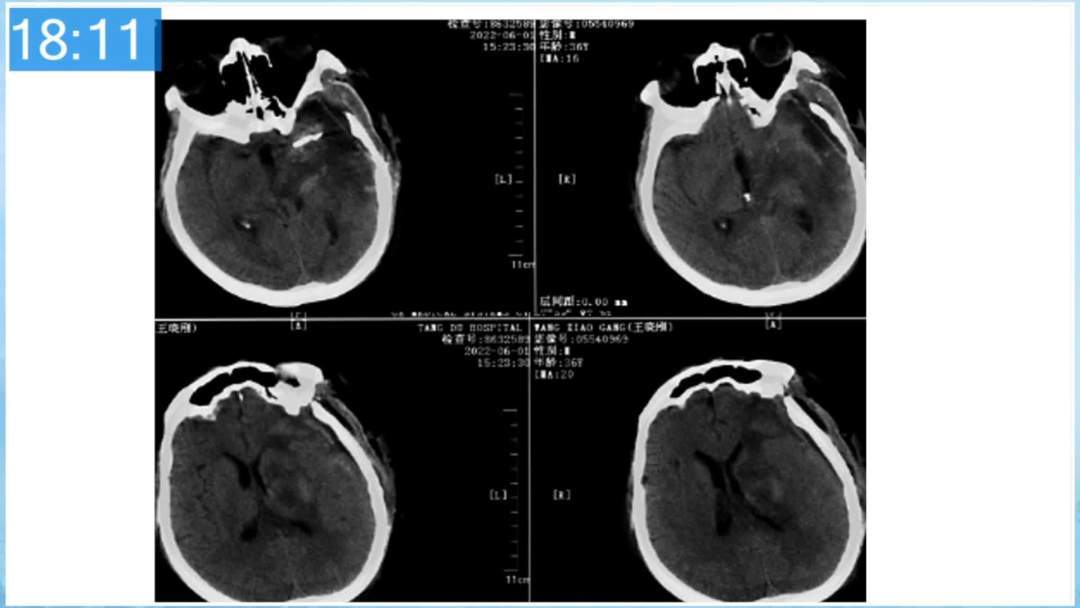

本期为大家特别分享:空军军医大学唐都医院邓剑平教授的精彩会议内容《颅内动静脉畸形的复合手术治疗》,欢迎大家阅读和分享!